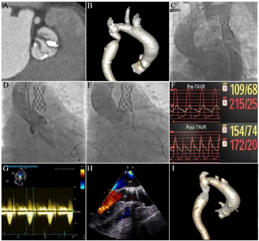

手术采用全身麻醉,气管插管、呼吸机辅助通气。首先穿刺右桡动脉,置入6F血管鞘,经右桡动脉送TIG导管至左、右冠状动脉开口造影提示左、右冠状动脉轻度粥样硬化,无严重狭窄病变。穿刺右股动脉,预埋两把缝合器(perclose proglide,雅培),经导管测得主动脉缩窄处前后峰值压差为35 mmHg。经右股动脉途径送入装载在BIB球囊上的CP支架(45 mm,美国NuMed公司)至主动脉缩窄处,确诊定位后释放。再次测得主动脉缩窄处前后压力阶差基本消失。颈部皮肤切开,游离左颈总动脉,穿刺左颈总动脉置入血管鞘,经颈动脉途径导丝跨瓣进入左心室,选择20 mm球囊扩张主动脉瓣,继而置入24 mm人工主动脉瓣(Vitaflow,上海微创)。术后即刻超声提示瓣膜形态良好,无明显瓣周漏。患者跨主动脉瓣压力阶差从术前100 mmHg降至12 mmHg(手术情况详见图1)。